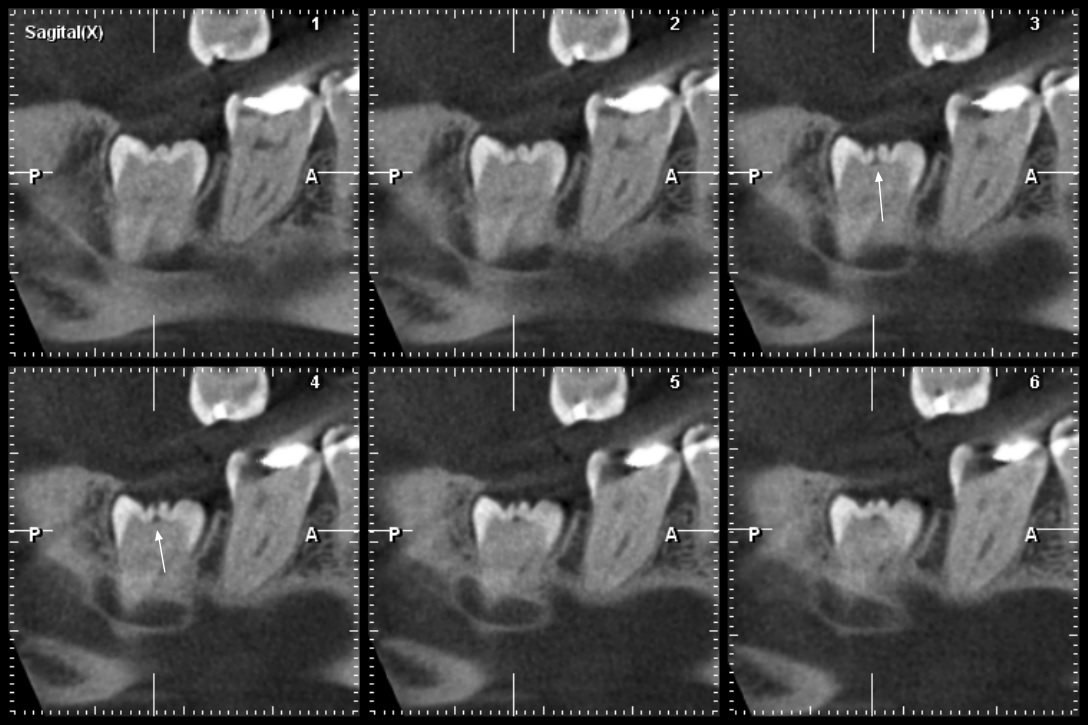

Se presenta la radiografía panorámica (2016) de una paciente femenina de 7 años de edad con un defecto de RIPE en el germen de la pieza 44, de localización distal y profundidad menor a ⅓ de la altura dentinaria (grado I) (figura 2). En la THC adquirida en 2022, con un tamaño de vóxel de 0,15 mm, se observó un defecto hipodenso en forma de fosa, localizado en el esmalte y la dentina (grado I) del tercio medio de la superficie distolingual (figura 3).

Se muestra la radiografía panorámica de una paciente femenina de 8 años de edad. Se observa la presencia de un defecto de RIPE en el germen dentario de la pieza 44, localización mesial y profundidad dentinal de grado I (figura 4). En la THC adquirida, con un tamaño de vóxel de 0,15 mm, se observó un defecto hipodenso de esmalte y dentina (grado I) ubicado en la vertiente mesial de la cúspide lingual (figura 5).

Se muestra la radiografía panorámica de una paciente femenina de 15 años de edad, en la que se observa la presencia de un defecto de RIPE de forma triangular bajo el esmalte de la cúspide distal de la pieza 38, de localización central y profundidad dentinal grado I (figura 6). En la THC adquirida, con un tamaño de vóxel de 0,2 mm, se observó un defecto dentinal de forma triangular y de grado I de profundidad, localizado en la cúspide distobucal, además de un defecto hipodenso del esmalte adyacente al defecto (figura 7).

Se tiene la radiografía panorámica de una paciente femenina de 45 años de edad, en la que se observa un defecto de RIPE en la pieza impactada 48, de localización mesial y profundidad dentinal de grado I, y, además, un segundo defecto ubicado en el centro de la corona y de forma alargada, que sería consistente con una fosa vestibular (figura 8). En la THC adquirida, con un tamaño de vóxel de 0,2 mm, se observó que el aparente defecto de RIPE mesial era, en realidad, la fosa mesiobucal y, además, se encontró un defecto de RIPE, grado I, en la cúspide distolingual asociada a un defecto hipodenso del esmalte adyacente al defecto (figuras 9, 10 y 11).

Los casos presentados constan de radiografías panorámicas y de THC, las cuales nos permitieron evaluar las superficies afectadas sin la superposición de estructuras anatómicas. Las radiografías panorámicas y bitewings fueron las técnicas radiográficas más utilizadas en el estudio de las características de la RIPE; la radiografía panorámica muestra en una sola toma todas las piezas erupcionadas y sin erupcionar, aunque las piezas anteriores, las premolares y molares maxilares, no se muestran de una manera adecuada; mientras que la THC puede demostrar la extensión real de los defectos (1). En todos los casos presentados, la THC ha demostrado la coexistencia del defecto dentinario y el defecto de esmalte; este signo tomográfico debería ser tomado en cuenta para estudios posteriores y en la planificación del tratamiento.

Al-Batayneh et al. (1) enfatizaron la importancia del diagnóstico tomográfico de los casos de RIPE. En los casos presentados, la discrepancia encontrada entre la radiografía panorámica y la THC podría ser determinante al momento de la planificación del tratamiento; se podría considerar la ampliación de estudio con THC en los casos confirmados de RIPE, para que se pueda determinar la extensión real del defecto y la decisión de intervención o espera.

En el caso 4, se observó la coexistencia de un defecto de RIPE y una fosa vestibular profunda. Hemos notado que las lesiones de RIPE tienen un mayor componente horizontal, mientras que la fosa vestibular profunda tiene un mayor componente vertical; tales diferencias podrían ser de utilidad al momento del diagnóstico diferencial.